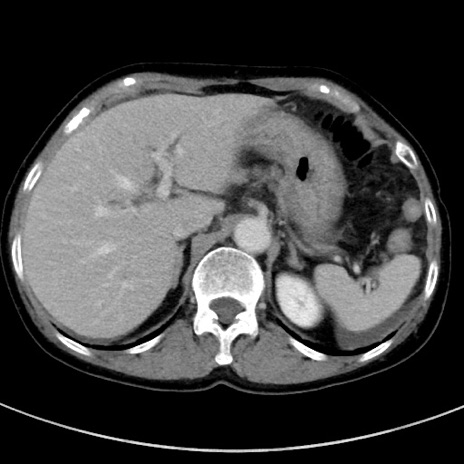

症例23(横断像)

【症例】70歳代女性

【主訴】下腹部痛・嘔吐

【現病歴】2日前より腹痛あり。昨日嘔吐あり。症状改善しないため来院。

【既往歴】胃GISTに対して胃部分切除後。

【身体所見】BT 37.1℃、BP 128/77mmHg、腹部:平坦・軟、下腹部に圧痛あり。

【データ】WBC 10200、CRP 0.31